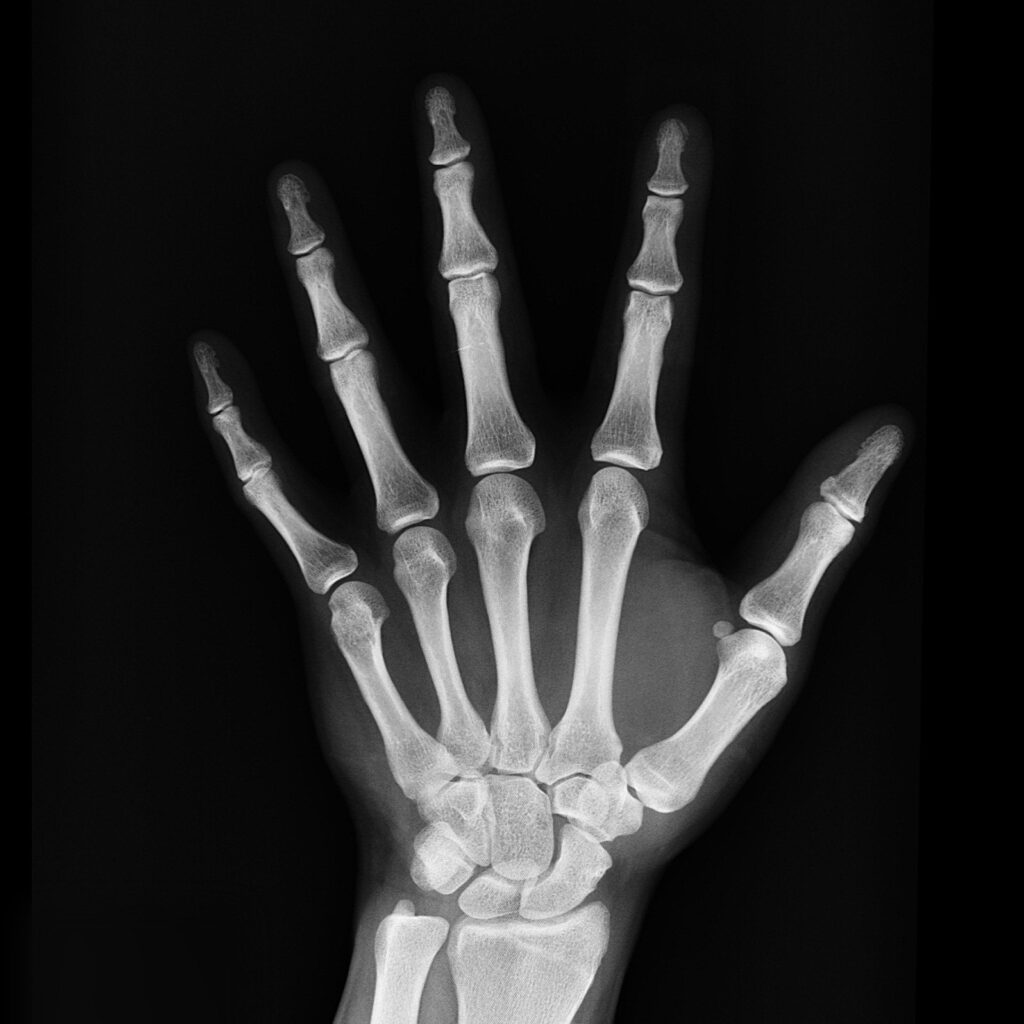

Here’s why. Not all of them do proper diagnostic testing and none of them treat based on the spines ideal structure. The gold standard for identifying the cause of these types of problems is weight bearing full spine x-rays. It’s not uncommon for your medical doctor or traditional chiropractor to take x-rays of only the area of complaint. For example, they only take neck x-rays for neck pain or low back x-rays for low back pain or sciatica. This is a BIG mistake. Your spine should be analyzed as one whole organ. This is very common due to insurance standards.

If your house has cracked walls, squeaky windows, and creaking floorboards you won’t investigate only one section of the foundation of your house. You check the whole thing. Your spine is the same. It is the foundation on which all your muscles and organs attach. In order for your chiropractor to properly investigate the cause of your disc herniation, headaches, low back pain, etc., x-rays of the entire spine are essential.

This is the exact same situation I see patients either put themselves in or are put in as a result of their medical doctor, physical therapist (who can’t take x-rays), or traditional chiropractor. All of these healthcare professionals are often very good at helping your symptoms. However, if you want to actually fix the foundation of your body you need a structurally focused corrective chiropractor to first examine your foundation via full spine x-rays.

I know numerous structurally focused chiropractic colleagues who take full spine x-rays of patients. We are a less common breed of chiropractor than the more common traditional, pain-based chiropractor. Those of us who do take full spine x-rays on all patients often see horribly degenerated, broken spines or spines with congenital defects that should never be adjusted without first having seen them on x-ray. As a result, it is VERY common for us to see patients that have come from traditional chiropractic offices with no relief. But when we take full spine x-rays the problem is all too often, quite obvious.

The risk of full spine x-rays is practically inconsequential when compared to the risk of not having them. You’re literally treating based almost entirely on feeling instead of visually objective evidence as with full spine x-rays. Without that evidence, you are left with only being able to adjust one or two segments at once. This is typically where you hear the infamous popping sound. The problem is those types of adjustments are only going to mobilize joints. It is essential for patients with abnormal spinal shapes to receive mirror-image adjustment where to adjust the entire neck or low back or even whole spine at once to retrain the body back towards an ideal spinal shape. This, of course, requires more than just regional, not segmental chiropractic adjustments. Chiropractic structural correction requires spinal remodeling and mirror-image spinal exercises and stabilization.

Full-spine x-rays are extremely safe and provide a very minimal amount of radiation. For more detail on the X-Ray Protocols and Exposure followed by Corrective Chiropractic CLICK HERE.